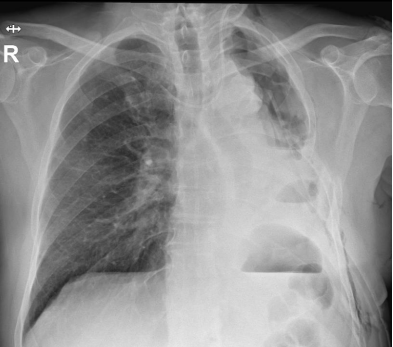

A 64-year-old gentleman underwent an upper left lobectomy with radical lymphadenectomy by left lateral thoracotomy and had an adjuvant chemotherapy for a pT2bN0 squamous lung carcinoma in 2018. He was admitted in our department with a proven recurrence in the remaining lower left lung and invasion of the main bronchus up to the carina. Enhanced CT-Scan revealed a complete left lower lung atelectasis and left shifted mediastinum (Fig 1). An intrapericardial left completion pneumonectomy, carinal resection and anastomosis between the proximal trachea and the distal right main bronchus stump were performed only through a left posterolateral thoracotomy. Anesthetic management consisted in thoracic epidural analgesia, an internal jugular central venous line, and a radial arterial catheter. Anesthesia was induced using propofol, ketamine, fentanyl, and rocuronium. The patient was intubated with a 37 Fr left double-lumen endotracheal tube (ETT) and maintained on propofol TCI to avoid sevoflurane contamination in the operating room. Thoracotomy was performed away from the previous scar, entrance in the pleural cavity was carefully carried out, pericardium abutting at the chest wall, hilar structures were individualized within the pericardium, left pulmonary artery and the inferior pulmonary vein were stapled, the bronchial tree was meticulously dissected with a digital dissection of the distal tracheal and right tracheal tree and with simultaneous lymphadenectomy. Tracheal was sectioned one cartilage above the carina and the right main bronchus between the first and the second cartilage. The specimen was extracted, a cross-field tube 5.0 mm cuffed endotracheal tube was used to intubate in the right bronchial tree and running suture was performed between trachea and  right main bronchus with 3.0 PDS. The patient was immediately extubated with less than 12 hours stay in intensive care unit. He underwent active physiotherapy, he had pain killers and preventive anticoagulation (Fig 2). He presented atrial fibrillation (on day 2) that was converted with medication. The control bronchoscopy performed on day 7 was satisfactory (Fig 3), he was discharged the same day. The definitive histopathology revealed a pT4N0M0 R0 squamous carcinoma.

Figure 1